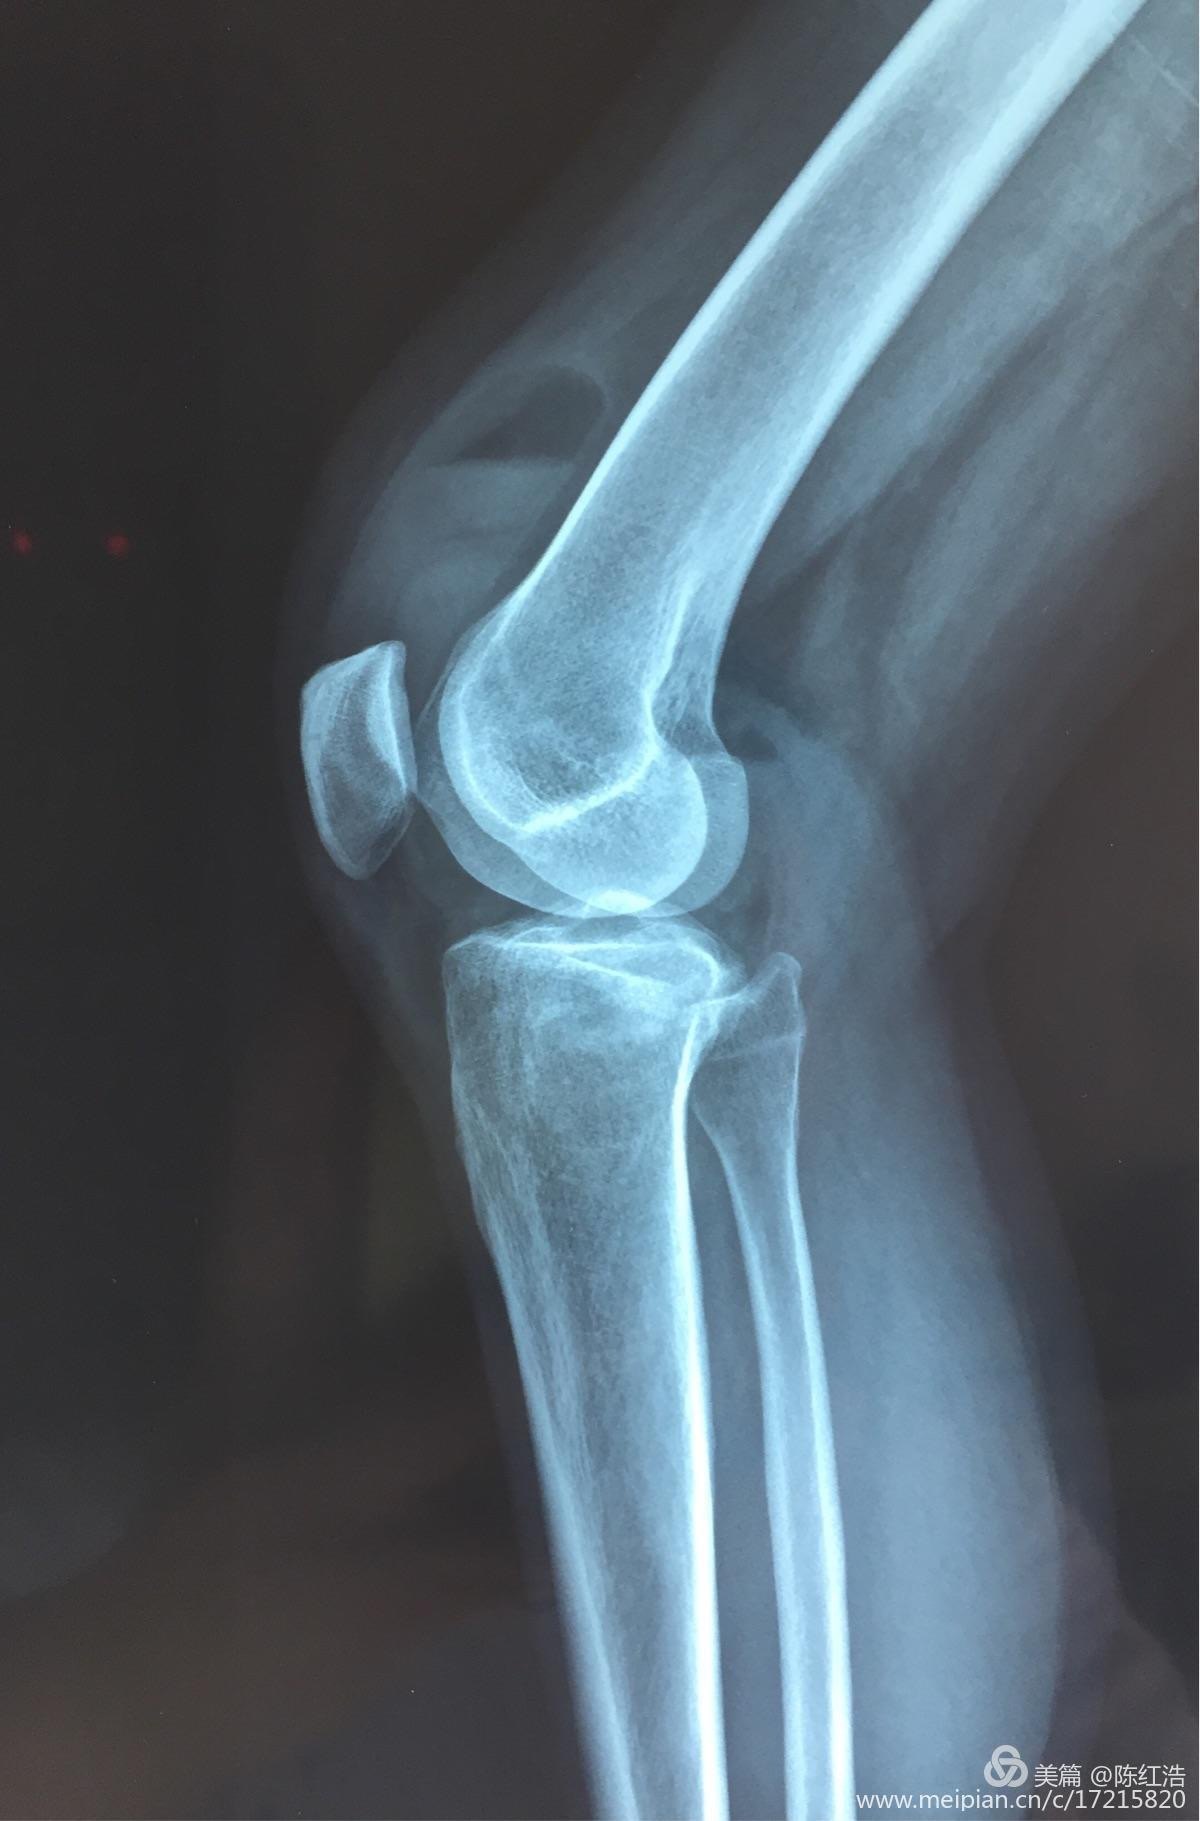

右胫骨平台粉碎性骨折 骨科与显微外科专业讨论版 爱爱医医学论坛

右胫骨平台骨折 胫骨平台骨折 伤感说说吧

右胫骨平台骨折图片 胫骨平台轻微骨裂图片 伤感说说吧

右胫骨平台骨折图片 搜狗图片搜索